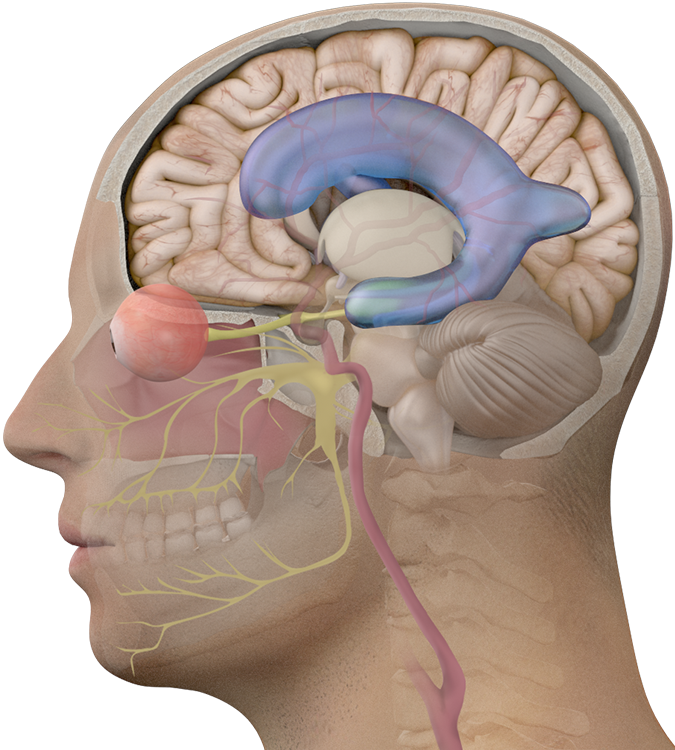

Choroid Plexus – The Definitive Guide | Biology Dictionary